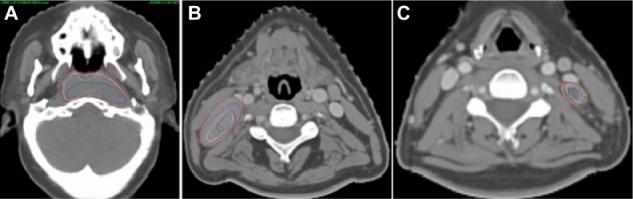

Twenty patients with locally advanced NPC who received concurrent (13 patients) or sequential (seven patients) chemoradiotherapy were prospectively recruited and underwent planning computed tomography (CT) and six repeat CTs (every five fractions). Each repeat CT was rigidly registered to the planning CT. Gross tumor volume (GTV) and elective clinical target volume (CTV) were manually delineated on each axial CT image. CTVs of the primary tumor and lymph nodes were expanded with 5 mm margins to corresponding GTVs, with necessary modifications. Volume loss, system and random errors, and the mean and three-dimensional vector displacements were calculated and compared statistically.

Volumes of the primary tumor and small (>1 cm, ≤3 cm) and large (>3 cm) positive neck lymph nodes decreased at a rate of 2.6%, 3.7%, and 3.9% per treatment day, respectively. CTVs of the primary tumor, lymph nodes, and elective region decreased 1.5%, 2.3%, and 0.3% per treatment day, respectively. Average displacements of the GTVs and CTVs were <1.3 mm in all directions. GTVs and CTVs of the large and small lymph nodes shifted medially by 0.8-1.3 and 0.6-1.2 mm, respectively, on average. Average three-dimensional displacements of the GTVs and CTVs were 3.4-4.3 mm and 2.5-3.7 mm, respectively. Volume loss and displacements in most directions were significantly larger in patients receiving concurrent chemoradiotherapy than in those receiving sequential therapy. Volume loss and displacements of the GTV of large nodes and elective CTV were significantly larger in male than in female patients.